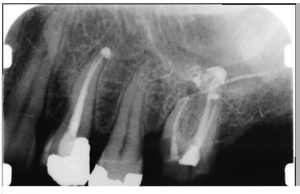

At your first appointment Dr. Dhayni will examine your teeth and take x-rays.  He will diagnose the cause of your toothache and recommend treatment.  If Root canal therapy is Dr. Dhayni’s recommended treatment, the severity of your infection will determine the length of treatment.  A root canal procedure involves removing the inflamed or infected pulp tissue, cleaning and reshaping the canal inside the tooth then filling and sealing the tooth.  Dr. Dhayni will use local anesthesia to numb the area near the tooth to reduce pain.

Root Canal Therapy costs approximately $600.00. The cost of a Root Canal depends on your extend of infection or inflammation and if you need restorative treatment such as a dental crown. We have various payment options and financing is available for those who qualify.  Dr. Dhayni uses the latest, most modern technology such as DIAGNOdent, digital x-ray technology and intraoral camera to provide the highest quality services to his patients.